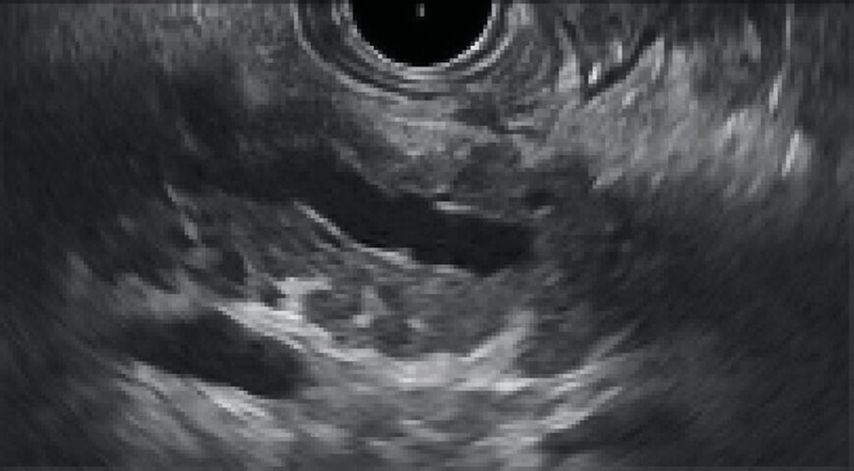

Abb. 1: Endosonografisches Bild einer chronischen Pankreatitis. Eigene Daten zeigen, dass die chronische Bauchspeicheldrüsenentzündung bei HIV-Infizierten häufiger als in der HIV-negativen Population vorliegt. Sie findet sich bei 21% der Untersuchten, während die Prävalenz bei Nichtinfizierten nach Literaturangaben bei max. 1‰ liegt (Göbbert A 2023).10 Dieser klinisch relevante Befund untermauert die These, dass das Krankheitsspektrum oft weit über den Status der HIV-Positivität hinausgeht. Die Komorbiditäten, die zusätzlich zur Grunderkrankung vorliegen, erfordern Zuwendung, diagnostische Bemühungen und konsequentes Management. Dies kann nur gelingen, wenn die Versorgung aktiv koordiniert bzw. gelenkt wird. Hier fungieren Infektiolog:innen als zentrales Stellglied